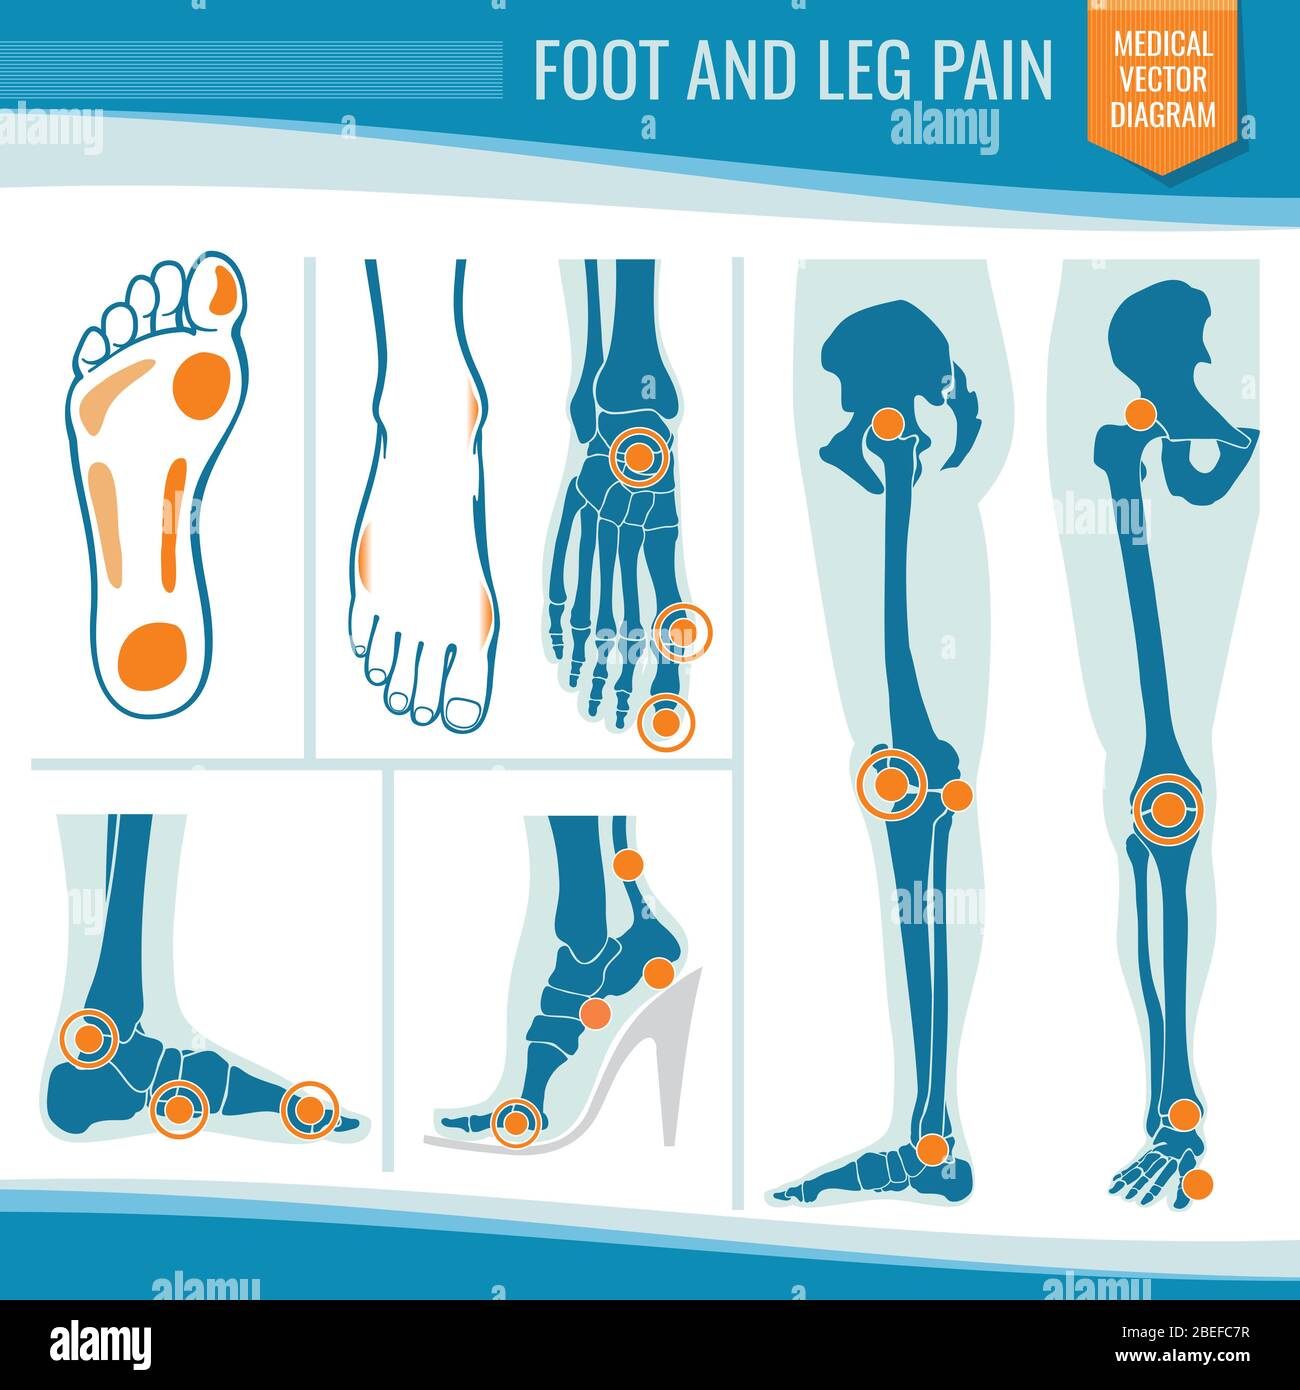

RF2BEFC7R–Douleur au pied et aux jambes. Arthrite et rhumatisme diagramme vectoriel médical orthopédique. Illustration de l'articulation des jambes rhumatismales